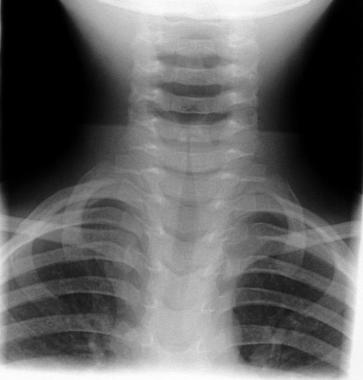

Croup, also known as laryngotracheobronchitis, is a viral infection that affects the respiratory system and causes inflammation and swelling to the voice box (larynx) area and gives sufferers a unique cough, hoarse throat and heavy breathing. It affects infants and children badly and although is a mild condition, it causes negative effects on the respiratory system as well as cold and flu-like symptoms. Croup is particularly bad at night and in the winter months but usually only lasts a few days.